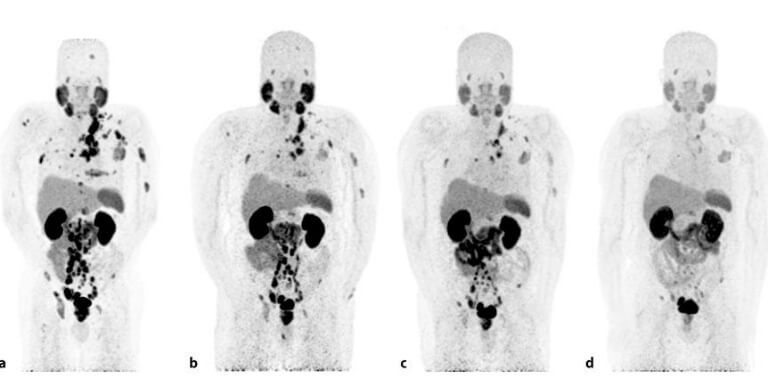

Medicina Nuclear: Tratamiento con PSMA-Lutecio

En UROVALLARTA contamos con tecnología de medicina nuclear de última generación, incluyendo el tratamiento con PSMA-Lutecio, una opción avanzada utilizada en Estados Unidos, Europa y en pocos centros en México.

Este tratamiento está indicado para pacientes con cáncer de próstata metastásico en etapas avanzadas, y consiste en administrar una sustancia radiactiva que se une específicamente a las células cancerígenas, liberando radiación directamente sobre ellas y eliminándolas de forma precisa, sin dañar en exceso los tejidos sanos.

El PSMA-Lutecio ha demostrado ser una alternativa eficaz para mejorar la calidad de vida y el control de la enfermedad en casos seleccionados.